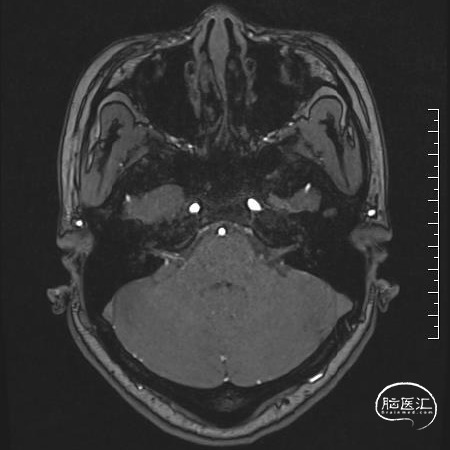

术前MRI:可见面神经REZ区有血管影,但是其信号与动脉信号有区别。同时因后颅窝解剖结构变异,乙状窦位置可能影响CPA区暴露

术前诊断:左侧面肌痉挛,考虑责任血管为:小脑前下动脉或脑干静脉

手术过程:常规侧卧位,乙状窦后发迹内直切口约6cm,星点前下方钻孔后铣刀游离骨瓣,磨钻扩大骨窗达乙状窦后缘,剪开硬脑膜后脑组织饱满释放脑脊液后仍不能显露CPA结构,遂将颅骨进一步磨除显露部分乙状窦,形成扩大乙状窦后入路,同时调整头位和显微镜进一步增加对CPA区的显露,在牵开小脑半球释放桥前池脑脊液后颅压下降脑组织塌陷。从后组颅神经处锐性剪开蛛网膜,暴露REZ区未见明显动脉压迫,只有小脑中脚静脉由桥脑于面听神经之间穿行后进入桥静脉汇入颈静脉孔。向后组颅神经腹侧、桥延沟及内听道处探查无动脉压迫,确认单纯静脉压迫。小块的垫棉小心垫于面神经和静脉之间后电生理提示除眼轮匝肌外其余LSR消失,电生理实时监护下反复调整垫棉位置最终LSR消失。水密缝合硬脑膜,骨瓣复位固定,各层严密缝合。术后患者清醒后面部抽搐未发作,听力正常,无面瘫。

通过查阅Rhoton anatomy我们认为此例病人责任血管为小脑中脚静脉。